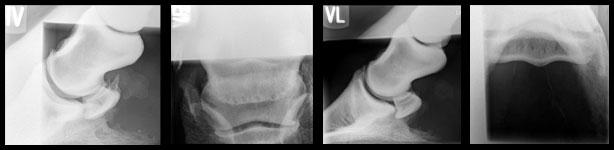

Vor zwei Jahren fing Phönix an taktunrein zu laufen und schließlich vorne rechts zu lahmen. Im Laufe eines Jahres war Phönix bei vier Tierärzten in Behandlung, davon in drei verschiedenen Kliniken. Es wurden alle möglichen Diagnosen gestellt, die keine waren. Teure Therapien die kein Ergebnis brachten. In Giessen dann die endgültige Diagnose: Podotrochlose- Hufrollenentzündung beidseits. Der Befund war so schlimm, dass ich mit den Tierärzten dort die Euthanasie von Phönix besprach. Eine Chance sollte er jedoch noch bekommen: Infusion mit Tildren und Stoßwellentherapie.

Nachdem auch dies keine ausreichende Wirkung hatte gab es nur noch eine Möglichkeit:

Jürgen Gerken! Gesagt getan. Er kannte das Pferd und ich kannte ihn. Mit Platten und ausreichend know-how läuft der Schimmel seit mehr als einem Jahr lahmfrei!